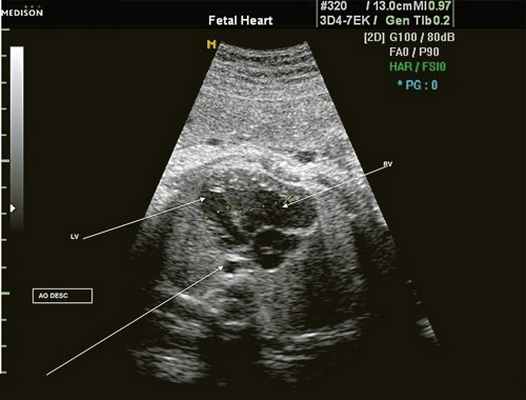

Исходя из особенностей внутрисердечной гемодинамики плода, для диагностики коарктации аорты были предложены косвенные признаки патологии в антенатальном периоде: дилатация правого желудочка и его гипертрофия (см. рис. 3), дилатация легочной артерии [6, 7, 14]. Авторы считают, что это достоверные признаки и встречаются они достаточно часто (в 18 из 24 случаев верифицированных диагнозов коарктации аорты). Поэтому была предложена оценка индексов отношения полости правого желудочка к левому (в норме - 1,1) и легочной артерии к аорте (у здоровых - 1,2). Исходя из увеличения этих параметров, можно предположить наличие затрудненного выброса в аорту или гипоплазию дуги аорты. Тем не менее, по данным предложивших эти косвенные признаки авторов, такие изменения выявляются только в 30% наблюдений (рис. 4).

Рис. 4. Диспропорция размеров желудочков сердца при коарктации аорты. RV - правый желудочек; LV - левый желудочек; AO DESC - поперечное сечение нисходящего отдела аорты.

Во второй половине 90-х гг. было опубликовано несколько работ, посвященных изучению диагностической ценности увеличения правого желудочка и уменьшения левого желудочка при коарктации аорты. Авторы, опубликовавшие эти результаты [2], считают, что чем раньше проводится исследование (от 14-16 до 25 нед гестации), тем оно информативнее для диагностики коарктации аорты. Доказательством могут служить данные, полученные D. Brown и соавт. [15]. В представленных исследованиях коарктация аорты отмечена у 8 (62%) из 13 плодов с диспропорцией размеров желудочков до 34 нед и только у 6 (21%) из 29 плодов после 34 нед беременности. Несмотря на то, что более половины случаев коарктации аорты сопровождается диспропорцией размеров желудочков, что достаточно легко выявляется при изучении четырехкамерного среза сердца плода, во многих исследованиях в Норвегии она не была диагностирована, даже при обязательном скрининговом изучении размеров сердца до 18 нед беременности [9].